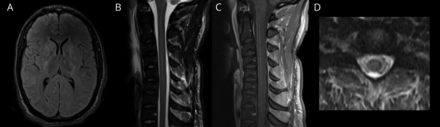

初步实验室结果,值得注意的是,低钠血症127毫克当量/ L和白细胞计数为9.4。腰椎穿刺脑脊液细胞增多了137白细胞淋巴细胞优势/毫升99%,166 mg / dL,蛋白质和葡萄糖的47 mg / dL。核磁共振成像的大脑和第四颈椎和胸椎钆对比显示,两国双边、片状T2 hyperintensities尾状,核,和内囊后肢以及纵向广泛T2-hyperintensity从上颈椎胸椎和帘线增强相关postcontrast成像(图)。

(一)Fluid-attenuated反转恢复轴向基底神经节的形象;(B) t2加权MRI矢状颈椎的系列;(C)与钆对比相应的t1加权MRI矢状;和(D)对应的轴向t2加权磁共振成像。

我们的病人表现出最常见的脊柱MRI发现自身免疫性GFAP astrocytopathy,纵向广泛T2 hypertensity。5虽然这也可以说明动,2因素区分自身免疫性GFAP astrocytopathy。为主,GFAP的脊髓增强欣赏薄,独特,沿着中央管和课程,对应antigen-enriched地区啮齿动物脊髓。2这是与动谱系障碍的朦胧的实质增强。而脊髓成像符合GFAP astrocytopathy,我们的病人的大脑成像没有揭示标志径向室周的增强欣赏在许多病人。

当面对成像,65%正确确定双边、片状T2 hyperintensities尾状,核、内囊后肢的轴向fluid-attenuated反转恢复序列和38%正确地确定了纵向广泛hyperintensity从上部颈椎胸椎和帘线增强t1相关联的颈椎矢状面MRI钆增强。最经常选择错误的答案是一个纵向广泛的脊髓损伤没有增强(22%)。